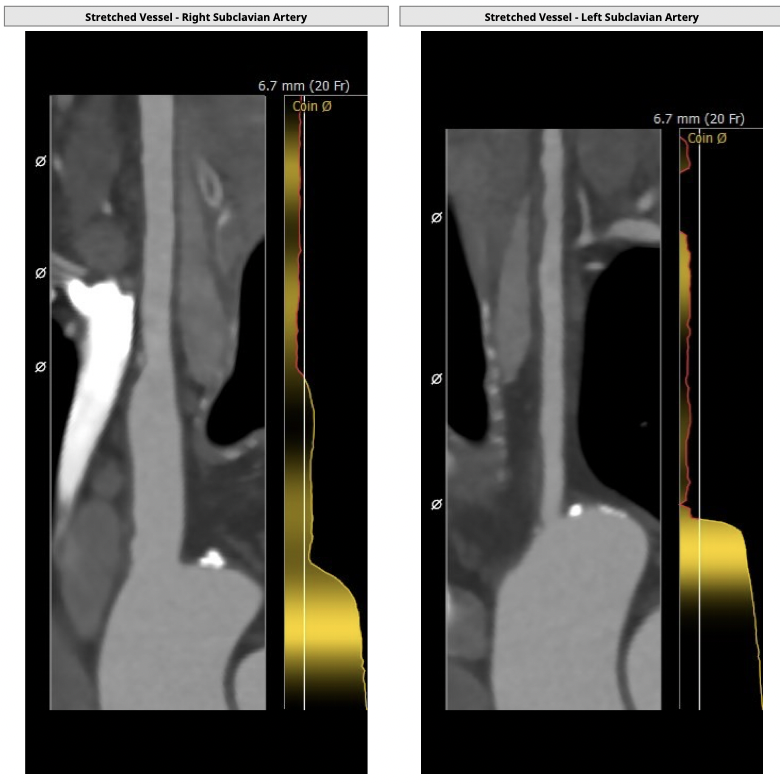

①患者因规律透析导致钙磷代谢紊乱,外周血管斑块钙化严重,最狭窄处仅2.8mm,通路建立难度极大(左右颈动脉均不符合入路条件);

确保冠脉安全,拟采取PCI+TAVR一站式手术策略,因患者右侧股动脉钙化严重、入路狭窄,拟采取无鞘法从右股动脉穿刺入路,选用20mm球囊预扩、L23号VenusA-Valve瓣膜、采用VenusA-Plus输送系统确保瓣膜的精确释放,瓣膜释放后结合造影和超声情况,决定是否后扩。